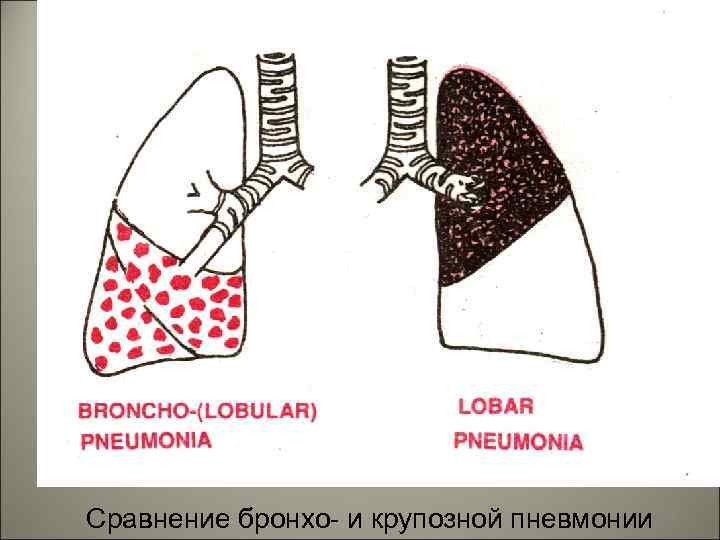

• Выделяют: 1. крупозную пневмонию, 2. бронхопневмонию, 3. аспирационную, 4. гипостатическую пневмонии, 5. интерстициальную пневмонию. 42

• Крупозная пневмония – острое инфекционно-аллергическое заболевание, при котором поражается одна или несколько долей легкого, в альвеолах появляется фибринозный экссудат, а на плевре – фибринозные наложения. 43

• При гематогенной: перитонит, гнойный менингит, метастатические гнойники в головном мозге, эндокардит с поражением трикуспидального клапана. 62

• Бронхопневмония – вторичная, очаговая пневмония. • Бронхопневмонией называется воспаление легких, развивающееся в связи с бронхитом или бронхиолитом. 63

• Экссудат по легким распределяется неравномерно, в одних альвеолах его много, в других – мало. В межальвеолярных перегородках – клеточный инфильтрат. Рентгенологически – очаговые затемнения, усиление легочного рисунка. Затемнение часто связано с бронхом. Характерна мозаичность поражения. 67

Сравнение бронхо- и крупозной пневмонии 68